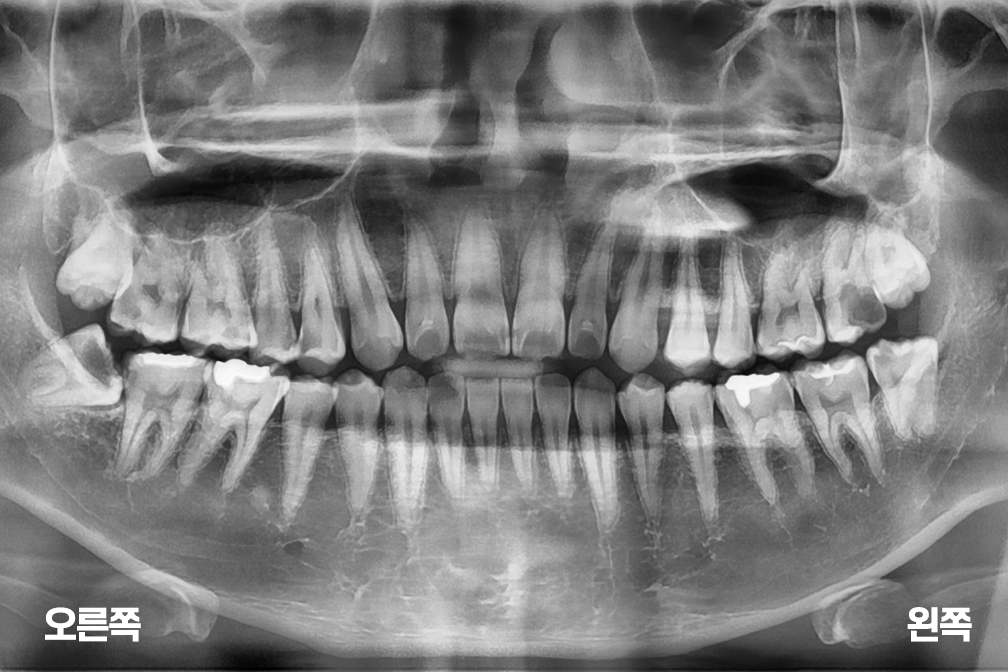

사랑니발치 사랑니 4개 발치

사랑니 발치